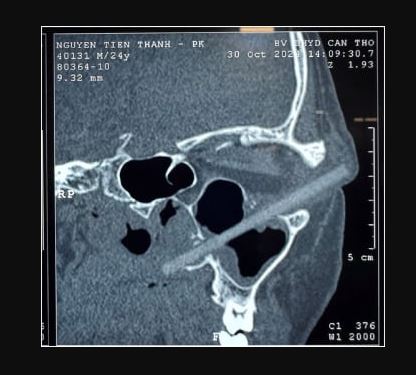

قاد هذا الأمر الرجل إلى مستشفى جامعة كان ثو، حيث أكد الأطباء مرة أخرى أن بصره 10/10، دون وجود علامات على إصابة مقلة العين، ومع ذلك، بدت العين اليسرى منتفخة وكان هناك إفرازات صديدية صغيرة من زاوية عينه اليسرى، أظهر فحص التصوير المقطعى المحوسب اللاحق وجود جسم غريب بطول 9 سم عالق فى تجويف عينه.

التصوير المقطعي للعين